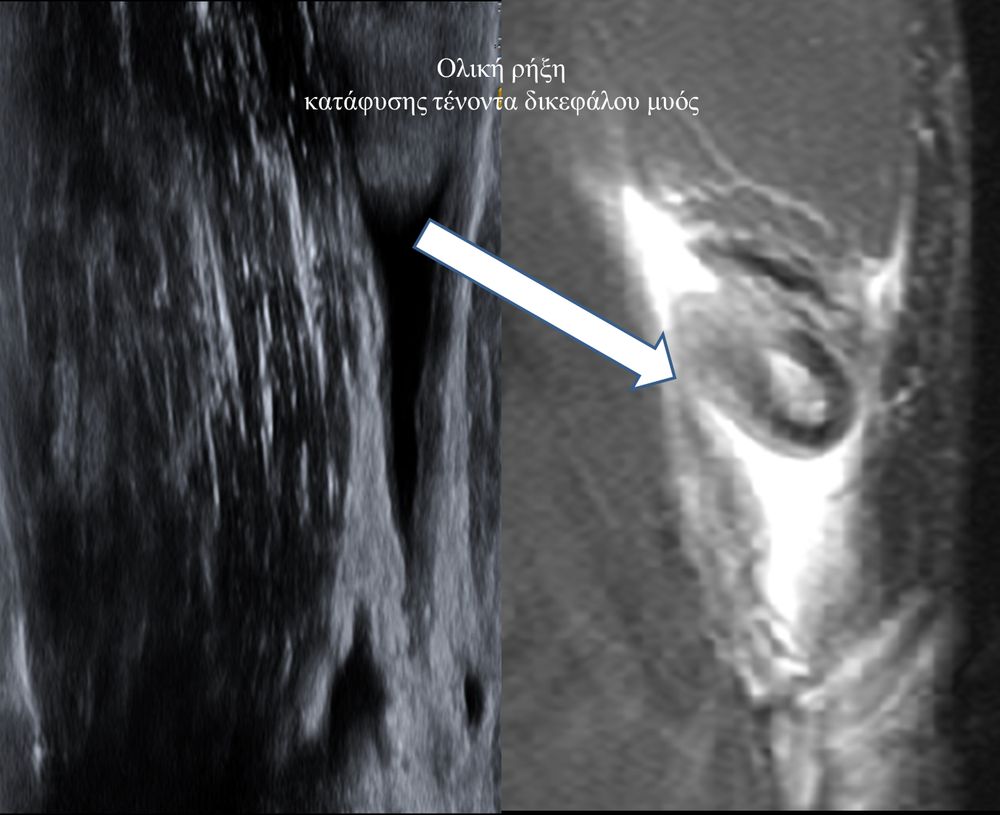

Είναι μια νέα μέθοδος που χρησιμοποιεί υψηλής ευκρίνειας υπερήχους για τη διάγνωση μυοσκελετικών παθήσεων που αφορούν τένοντες, μυς, συνδέσμους, νεύρα και περιφερικές αρθρώσεις. Η μέθοδος αναπτύχθηκε τα τελευταία χρόνια και αποτελεί αναπόσπαστο μέρος στη διαφορική διάγνωση παθήσεων που αφορούν τηνορθοπαιδική, αθλητιατρική, ρευματολογία και παιδιατρική.

Πρόκειται για υπερηχογράφημα υψηλής ευκρίνειας που επιτρέπει την λεπτομερέστατη απεικόνιση (σε επίπεδο χιλιοστού) ακόμη και πολύ μικρών/επιφανειακών ανατομικών δομών και απαιτεί ειδικό υπερηχογραφικό εξοπλισμό καθώς και εξειδίκευση του ακτινολόγου. Η εξέταση γίνεται με δυναμικό τρόπο, δηλ εκτελούνται δοκιμασίες κίνησης του μέλους που πάσχει, ώστε να αποκαλυφθεί η παθολογίαακόμη και όταν δεν είναι εμφανής σε θέση ηρεμίας. Επιπλέον, η εξέταση είναι ανώδυνη και ασφαλής και δεν περιλαμβάνει ακτινοβολία (CT), μαγνητικό πεδίο (MRI) ή παραμονή σε κλειστό χώρο και είναι πολύ ανεκτή τόσο σε ενήλικες όσο και σε παιδιά.

- Αγκώνα (πχ επικονδυλίτιδα)